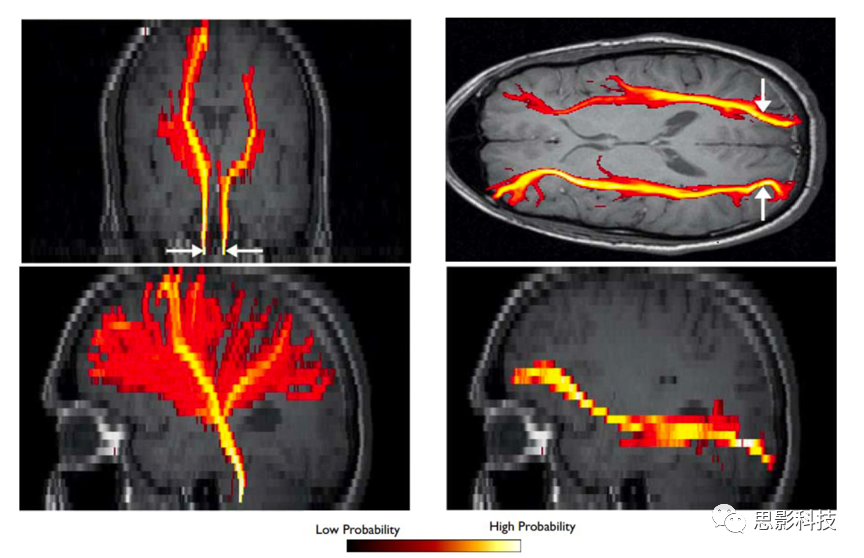

概率性纖維追蹤主要通過球棍(ball & stick)模型結合馬爾科夫鏈蒙特卡洛模擬(MCMC)方法估計纖維束方向在每個體素上的概率分布,通過在每個種子點體素發(fā)射上千條纖維束的方法來追蹤纖維束的后驗分布,并計算纖維束的連接概率、平均FA等相關指標。

圖例:概率性纖維追蹤